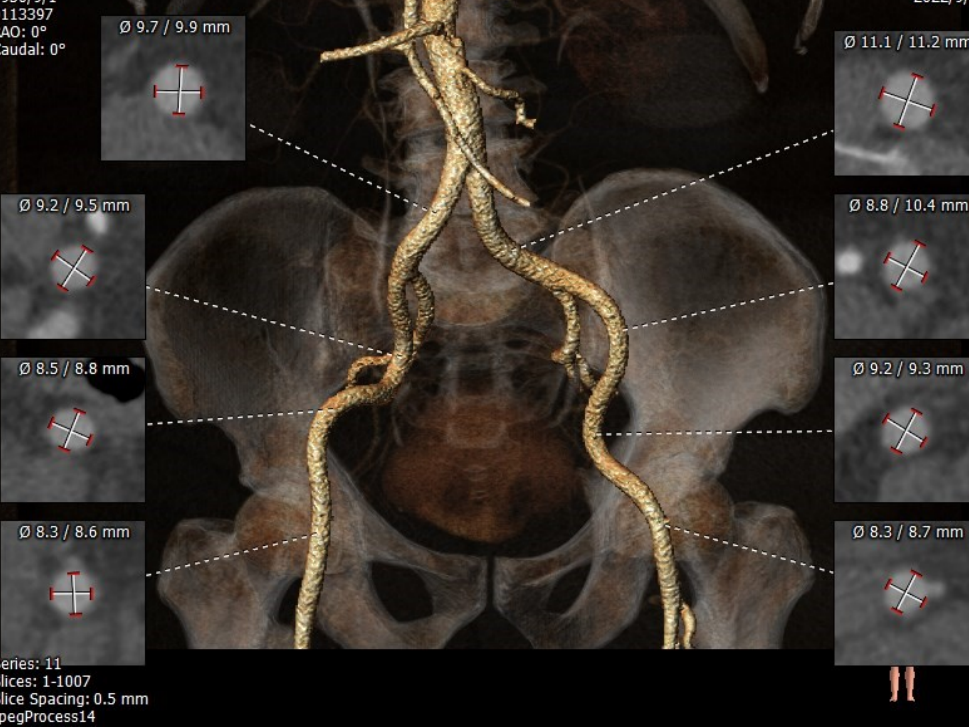

CT测量

主动脉根部CT测量

瓣环周长平均直径:26.5mm

LVOT周长平均直径:24.8mm

瓣环上4mm平均直径:23.6mm

瓣环上6mm平均直径:23.0mm

升主动脉平均直径:31.8mm

瓣环角度:33°

窦管结合部平均直径:29.7mm

窦部长径:29.6mm;短径:23.5mm

左冠开口高度:16.1mm

右冠开口高度:16.1mm

左瓣叶长度:15.4mm

右瓣叶长度:15.1mm

钙化指数:1182.2mm³

主动脉瓣钙化分布

入路情况

股动脉入路轻度迂曲

• 瓣环周长为82.8mm,平均径为26.5mm;LVOT周长为78.3mm,平均径为24.8mm;

• 主动脉瓣重度钙化,钙化主要分布于瓣叶及瓣叶交界处;钙化从瓣环延伸至流出道9.7mm;

• 股动脉入路条件尚可,轻度迂曲,无明显钙化团块。